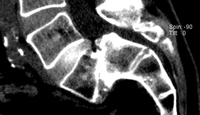

Erkrankungen der Wirbelsäule und der angrenzenden Strukturen bei Kindern oder im Wachstumsalter können sich ohne erkennbare Ursache entwickeln oder die Folge einer Grunderkrankung sein. Obwohl gerade bei Kindern versucht wird, so lange wie möglich auf Operationen zu verzichten, können sie aufgrund der Auswirkungen der Wirbelsäulenerkrankung notwendig werden. Derartige Operationen stellen häufig einen erheblichen Eingriff dar, und benötigen eine gesonderte Infrastruktur mit speziellen interdisziplinären Möglichkeiten.

Als ein Zentrum der Maximalversorgung und damit großer Erfahrung werden im Zentrum für Wirbelsäulenchirurgie und Schmerztherapie auch alle kindlichen Erkrankungen und deren Folgen der Hals-, Brust- und Lendenwirbelsäule sowie der angrenzenden Strukturen konservativ oder mit entsprechenden Operationstechniken behandelt. Hierbei kommen alle operativen Zugänge von hinten, durch den Brustkorb oder den Bauch zur Anwendung. Infrastrukturell bestehen alle Möglichkeiten der hierauf ausgerichteten, interdisziplinären Zusammenarbeit (z. B. Kinderintensivstation, Kinderradiolge, Pädiatrie, Kinderpneumologe, Kinderkardiologe, Neuropädiater, Onkolge, etc.). Somit ist Tag und Nacht Maximalversorgung auch bei schwersten Operationen sowie eine effiziente Versorgung einer möglichen Grunderkrankung gewährleistet.